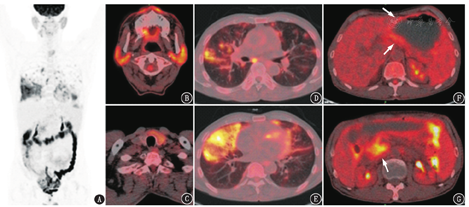

18F-脱氧葡萄糖(fluorodeoxyglucose, FDG)PET/CT显像如图1所示,可见多系统病变:(1)双侧腮腺、右侧颌下腺(左侧已切除)肿胀,代谢弥漫增高[最大标准摄取值(maximum standardized uptake value, SUVmax)4.6];(2)双肺有大小不等的代谢增高斑片、实变及磨玻璃影(SUVmax 10.8),部分病变伴"铺路石征";(3)胰腺形态饱满且代谢增高,以胰头及钩突为著(SUVmax 5.6);(4)胃体及胃窦部胃壁增厚、代谢轻度增高(SUVmax 2.9),结直肠及部分小肠节段性代谢增高,以自直肠至结肠肝曲为著;(5)甲状腺左叶及峡部有代谢增高的低密度结节(SUVmax 4.8);(6)纵隔及肺门有代谢增高的小淋巴结(SUVmax 6.3)。

先从PET/CT影像角度分析。病变具有代谢活跃的特点,累及腺体(唾液腺、甲状腺、胰腺)、肺、消化道、淋巴结,其中肠道的代谢需与生理性摄取鉴别;淋巴结分布在肺门和气管周围,需与非特异性炎性淋巴结鉴别。因此,疾病鉴别诊断主要依据腺体(尤其是唾液腺和胰腺)、肺的病变特点进行。良性病变中,容易累及唾液腺、胰腺、肺的疾病是IgG4相关性疾病,恶性病变则主要鉴别淋巴瘤。另外,患者唾液腺的病变加上口干、眼干的症状,需考虑干燥综合征的可能,原发性干燥综合征不伴发其他疾病,而继发性干燥综合征则可伴发其他风湿性疾病,如类风湿关节炎、系统性红斑狼疮,也可伴发淋巴增殖性疾病。

18F-FDG PET/CT诊断IgG4相关性疾病有几个要点:(1)典型的主要受累脏器和部位如胰腺(弥漫或节段性受累)、胆道系统、泪腺及眼眶周围、唾液腺,并出现主动脉周围炎/腹膜后纤维化/纵隔纤维化,同时存在多个典型脏器受累具有较强的诊断意义。(2)注意IgG4相关性疾病可解释的其他次要病变,即有些脏器或部位的IgG4相关性疾病影像诊断特异性不强,或者需要与其他更常见的疾病鉴别。例如前列腺病变虽可为IgG4相关性疾病的表现,但在老年男性患者中需先鉴别前列腺癌;肺部、肾、淋巴结病变影像特点不强,在其他疾病如淋巴瘤中也容易出现。这些次要病变的表现需与IgG4相关性疾病的总体特点相符。当出现IgG4相关性疾病罕见的受累脏器或部位时(例如睾丸、骨骼、脑实质、肾上腺等),或表现为罕见的影像表现时,疾病整体就难以用IgG4相关性疾病解释,需要先考虑其他方向的诊断。(3)临床表现与IgG4相关性疾病符合,如起病隐匿或亚急性起病,病灶进展慢,血清IgG4升高,病理表现吻合,激素治疗有效等。纵观本例,PET/CT上有较为典型的IgG4相关性疾病表现(胰腺、唾液腺弥漫受累),MRI和超声内窥镜检查也提示自身免疫性胰腺炎,肺、消化道、淋巴结病变可以符合IgG4相关性疾病表现,多个脏器的活检虽未提示IgG4相关性疾病的典型病理特征,但均为慢性炎且未见肿瘤,临床曾予激素治疗症状有缓解。以上病例特点都与IgG4相关性疾病相吻合。

患者之后行胃镜,见胃体黏膜粗糙,多发小结节样隆起及散在浅溃疡,活检病理提示黏膜相关性淋巴瘤。再行经支气管镜肺活检,亦提示黏膜相关性淋巴瘤。临床予利妥昔单克隆抗体+环磷酰胺+表阿霉素+长春地辛+泼尼松(R-CHOP方案)化疗4程后复查PET/CT,肺、胃肠道、胰腺、甲状腺病变基本消失,淋巴结代谢减低,唾液腺肿胀好转、代谢减低。